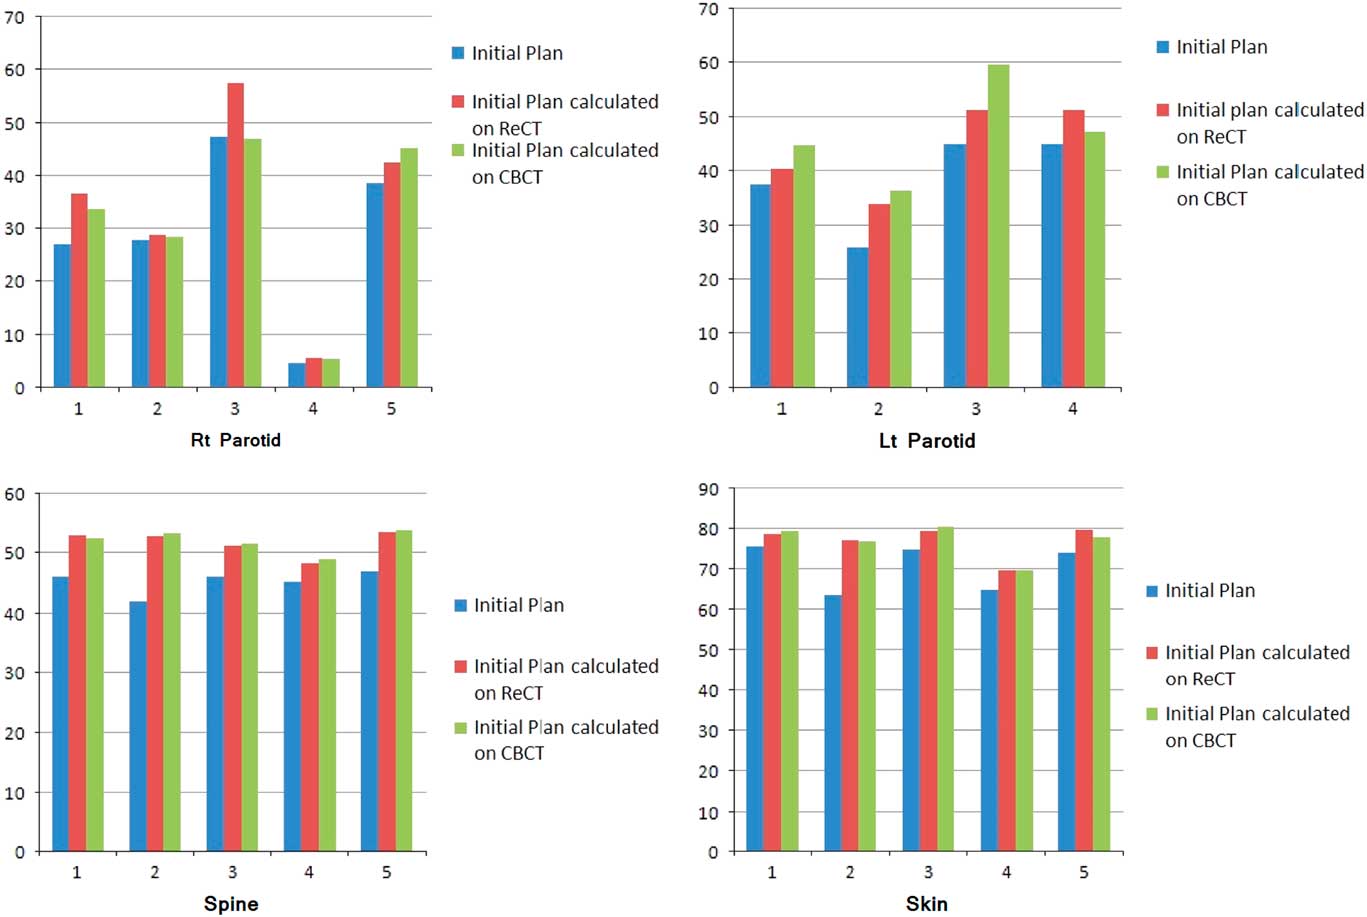

Re-scanning and re-planning at 20th fraction of the treatment shows 27% (13–42%) reduction in parotid volumes (Figure 2), and therefore 21% (7–35%) increase in parotid mean doses. Initial plan calculated on ReCT and CBCT found 15% (9–26%) increase in planning risk volume (PRV) spine maximum doses, which were reduced by re-planning on ReCT. The body maximum doses increased by 6·5% (4–8%) in four patients and 22% in one patient when initial CT plan was calculated on ReCT and CBCT. These results showed a statistically significant difference in the parotids, PRV spine and skin doses with a p-value of 0·01, 0·007 and 0·02, respectively. Figure 3 is the graphical representation of mean doses of parotids and maximum doses of PRV spine and skin in all three plans (initial CT plan, initial plan calculated on ReCT and CBCT).

Figure 3 Graphical representation of mean doses of parotids and maximum doses of PRV spine and skin in all three plans of five patients.